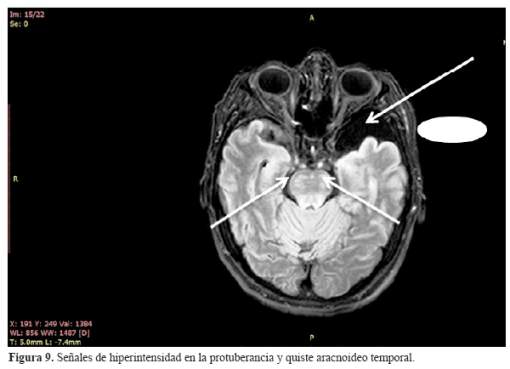

La exploración neurológica mostró marcadas alteraciones en la esfera emocional, adoptando un comportamiento infantil, con variaciones en el ánimo y en el interés para realizar el test, minicognitivo de Folstein así como, a los resultados en cada uno de los ítems conocidos, en los que frente a las fallas, no le suscitaban incomodidad o ansiedad . La puntuación de la prueba neuropsicológica fue de 8 puntos con fallas en la orientación temporal , mencionando sólo el día de la semana, estaba desorientada en lugar y tuvo groseras fallas en la memoria inmediata retuvo dos de tres palabras y al minuto las olvidó completamente; nivel de atención igualmente afectada finalmente en la copia de los pentágonos entrelazados graficó un pentágono adjunto a un cuadrado. Presentó anhedonia frente a los resultados. No tuvo afasia, apraxia ni agnosia. Presentó incoordinación y adiadocinesia asimétrica, marcha atáxica zigzageante. Moderada debilidad en la fuerza muscular contra resistencia que se acompañó de reflejos vivos y ausencia de los signos de Babinski y el de Hoffmann. La exploración de la sensibilidad supeficial y profundas normales. Concluyéndose clínicamente el compromiso del vermis y los hemisferios cerebelosos, puso en evidencia el estado demencial al obtener una puntuación de ocho en el test de Folstein, no disartria, incoordinación axial y de los miembros y la marcha zigzageante, Cuadriparesia moderada en los miembros, sin signos patológicos, reflejos tendinosos presentes. Con estos resultados se produjo la exploración mediante resonancia magnética del cerebro (RM) contrastada , incidiendo en T1,T2 y el FLAIR, que mostró: atrofias comprometiendo las regiones fronto – témporo – parietales, el cuerpo calloso y el cerebelo ( figura 6 ). En la incidencia con el FLAIR se observó: hiperintensidad en las cápsulas internas, pedúnculos cerebrales y en las fibras transversas de la protuberancia. En forma accidental el hallazgo de un considerable quiste aracnoideo temporal izquierdo que no tuvo mayor implicancia clínica en el estado de la paciente (figura 6, figura 7, figura 8 y figura 9)

Los xantomas tendinosos aquilianos, biopsiados mostraron la naturaleza de la enfermedad, al igual que la presencia del arco senil tempranamente aparecidos, antes de los 30 años, las cataratas, la presencia de xantoma en el cuerno ventricular derecho por la especialidad y la osteoporosis estarían indicando un estado avanzado de la enfermedad por XCT. El estudio con resonancia magnética del cerebro (RM), puso en evidencia los cambios morfológicos del tejido cerebral, asi como , la penetrancia del colagenol en estructuras específicas empleando la incidencia del FLAIR.

El estudio mediante el empleo de la resonancia magnética cerebral fue decisivo para explicar las alteraciones anteriormente precisadas e interpretar la etiología al visualizarse la presencia del colastenol en diferentes localizaciones del tronco encefálico, así como, las regiones atróficas de los hemisferios cerebrales comprometidas y que explicaban la demencia como la ataxia.